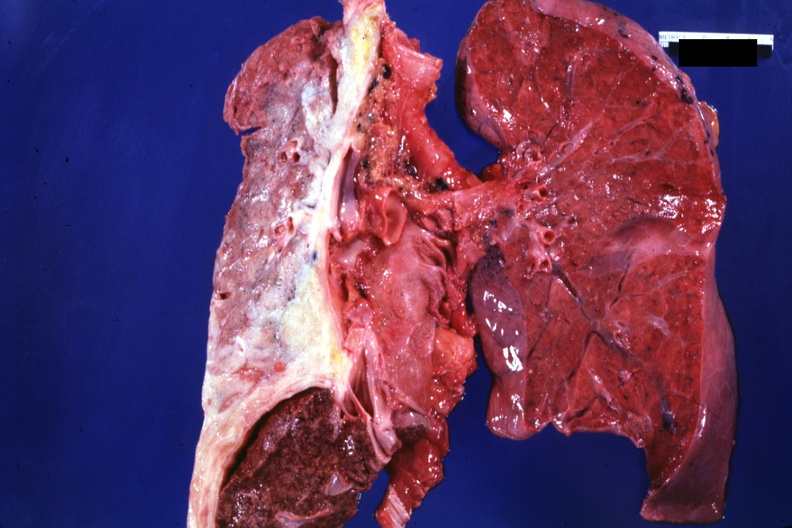

31855/33648

GROSS: RESPIRATORY: Lung: Mesothelioma: Gross very good contrast uninvolved left lung with tumor in right lung